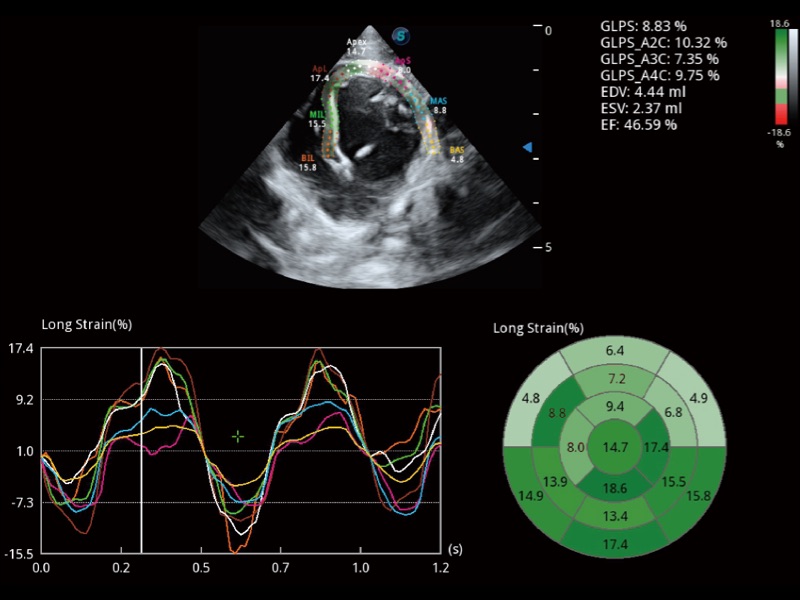

能夠基于左心室壁追蹤和辛普森法,自動計(jì)算射血分?jǐn)?shù),支持多個可移動點(diǎn)描跡,與手動測量相比,極大節(jié)省了動物醫(yī)生的時間和精力。

具備多種協(xié)議可選,同時支持17階段劃分法和專業(yè)的SE報(bào)告。